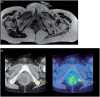

The purpose of this article is to familiarize the reader with the anatomy of the major pelvic nerves and the clinical features of associated lumbosacral plexopathies. To demonstrate this we illustrate several cases of malignant lumbosacral plexopathy on computed tomography, magnetic resonance imaging, and positron emission tomography/computed tomography. A new lumbosacral plexopathy in a patient with a prior history of abdominal or pelvic malignancy is usually of malignant etiology. Biopsies may be required to definitively differentiate tumour from posttreatment fibrosis, and in cases of inconclusive sampling or where biopsies are not possible, follow-up imaging may be necessary. In view of the complexity of clinical findings often confounded by a history of prior surgery and/or radiotherapy, a multidisciplinary approach between oncologists, neurologists, and radiologists is often required for what can be a diagnostic challenge.